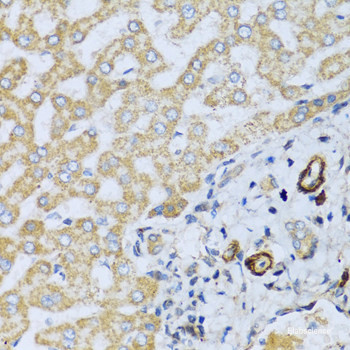

Product information "Anti-CSH1"

The protein encoded by this gene is a member of the somatotropin/prolactin family of hormones and plays an important role in growth control. The gene is located at the growth hormone locus on chromosome 17 along with four other related genes in the same transcriptional orientation, an arrangement which is thought to have evolved by a series of gene duplications. Although the five genes share a remarkably high degree of sequence identity, they are expressed selectively in different tissues. Alternative splicing generates additional isoforms of each of the five growth hormones, leading to further diversity and potential for specialization. This particular family member is expressed mainly in the placenta and utilizes multiple transcription initiation sites. Expression of the identical mature proteins for chorionic somatomammotropin hormones 1 and 2 is upregulated during development, although the ratio of 1 to 2 increases by term. Mutations in this gene result in placental lactogen deficiency and Silver-Russell Protein function: Produced only during pregnancy and is involved in stimulating lactation, fetal growth and metabolism. Does not interact with GHR but only activates PRLR through zinc-induced dimerization. [The UniProt Consortium]

| Application: | IHC |

| Immunogen: | Recombinant protein of human CSH1 |